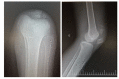

FES-assisted cycling has been recommended to people struggling to emerge from a disability to more functioning life after spinal cord injury. Recommendations issued by a gowing number of scientific papershas promised toimprove body composition and physical activity levels, as well as to controlinvoluntary muscle response; favoring activity and participation which break new grounds in expanding locomotion, leisure and occupational options for people with paraplegia and tetraplegia. In this report we described our experience to select and prepare a pilot to compete in the FES Bike Race modality at Cybathlon 2016 in Kloten (Zurick). He was a man, 38 years old, with a complete spinal cord injury, level T9, three years of injury. He took part in a two preparation phases lasting respectively 18 and 12 weeks each: (1st) pre-FES-cycling and a (2nd) FES-cycling. The 1st phase aimed to explore electrical stimulation response in the quadricps, hamstrings and gluteus muscles; searching for a standard muscular recruitment enable to propel the pedals of a trike. Following, in the 2nd phase, stationary to mobile FES-cycling was performed at the same time the development of the automation and control systems were being incorporated in the trike. We adapted a commercial tadpole trycicle anda pilot controlled system. Although we had planned a three session by week protocol, for reasons of term and time to finish the trike development and be prepared to compete, in the last two weeks before the Cybatlhon an intense level of exercise was maintained. After the race, we noticedinflammatory signs on the left knee which later revealed a patella fracture. The video footage analysis confirmed ithappened during the race's first lap.